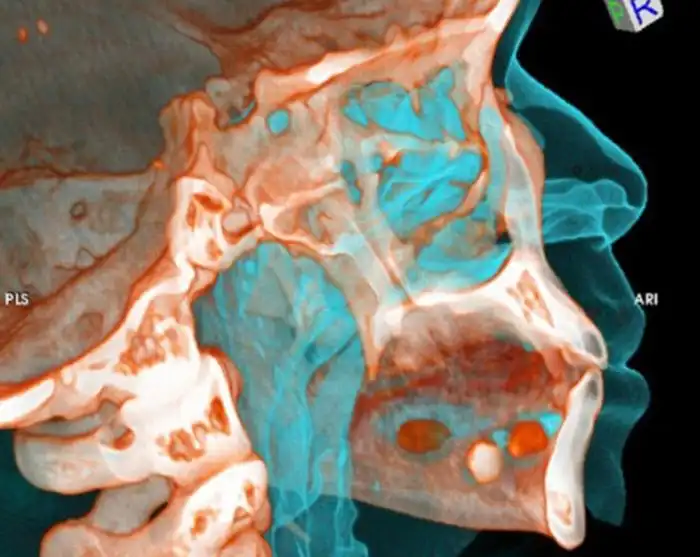

Девять пакетов кокаина

Попытка провезти кокаин под языком

Одна часть кокаина под языком, а вторая в желудке